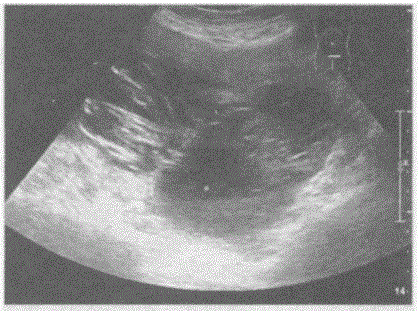

问题 临床资料:女,69岁,自诉下腹部疼痛,排便困难。 临床物理检查:右下腹可扪及一肿物,质硬,边界清,活动度好,有压痛。 超声综合描述:子宫前位,形态大小如常,肌壁回声均匀,内膜厚度0.3cm。腹、盆腔可见无回声区,上界平脐,下至耻骨联合,形态不规则,内呈网状,分隔多且厚薄不均,CDFI:分隔上可见条状血流信号,PW:呈动脉频谱,RI=0.54。

选项 A.腹盆腔多房囊性占位(卵巢癌) B.畸胎瘤 C.腹盆腔结核 D.腹盆腔包裹性积液

答案 A